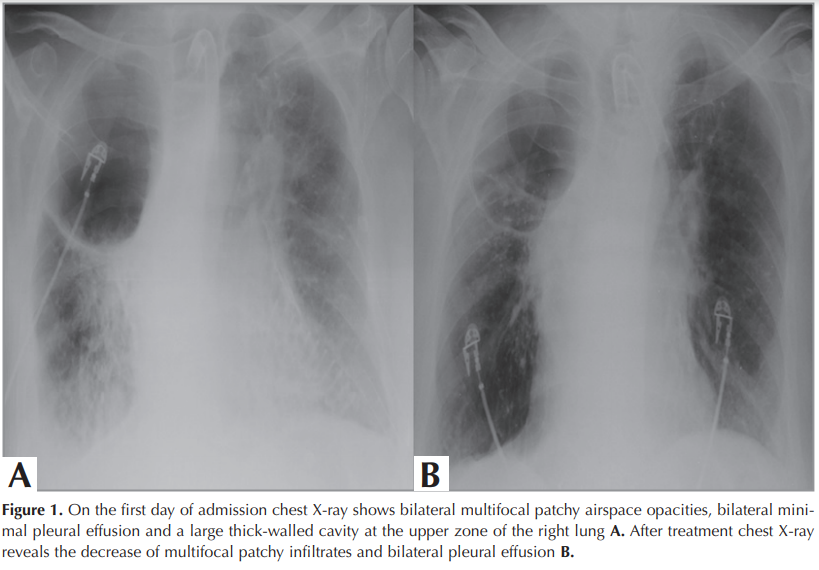

The patient was admitted to the hospital with shortness of breath, fever, and increased tracheal secretions for the last two weeks. The patient had neither traveled outside of Turkey nor had been exposed to anyone with suspected or confirmed diagnosis of COVID-19. Physical examination was remarkable for ronchi bilaterally. Heart sounds were normal. His vital signs included a temperature of 37.8°C, blood pressure of 110/75 mmHg, heart rate of 87/minute, respiratory rate of 21/minute, saturation of 90% on MV with SIMV mode and FiO2 50%. Laboratory results were as follows; white blood cell count (WBC) of 15.02x109/L, a hemoglobin (Hb) level of 11.6 g/dL, a lymphocyte count of 0.21 x109/L, and a platelet count of 203x109/L. A large cavity at upper zone of the right lung and heterogenous opacities at middle and lower zones of the both lungs were seen on chest X-ray (Figure 1 A). Chest CT showed bilateral peripheral multifocal rounded consolidation and ground glass opacities (GGO) and tree in bud opacities with centrilobular nodules. Also there was a cavity at lateral basal segment of the right lower lobe The peripheral and multifocal rounded consolidation and GGO are the typical findings of COVID-19 pneumonia. The other findings are atypical for COVID-19 pneumonia and point to a bacterial, mycobacterial or viral infection other than COVID-19 pneumonia (Figure 2). Parenteral antibiotic treatment was initiated empirically. SARS-CoV-2 RT-PCR analysis of two consecutive combined NP/OP swabs was reported negative. Even though RT-PCR results were negative twice, the patient was considered compatible with COVID-19 pneumonia with radiological and clinical features. Therefore; he was accepted to the intensive care unit (ICU) and isolated. Rapidly; hydroxychloroquine 200 mg b.i.d. and azithromycin 500 mg q.i.d were initiated for probable COVID-19 and piperacillin/tazobactam were started empirically owing to a probable bacterial co-infection. By the tracheostomy cannula, mechanical ventilation was continued. Subcutaneous low molecular weight heparin (LMWH, enoxaparin) 6000 U b.i.d was applied. After two days, he deteriorated clinically. He had subfebrile fever, tachypnea and was hypotensive with need of vasopressors. CRP and procalcitonin levels had increased, so ETA bacterial culture and viral PCR examinations were repeated. Antibiotic regimen was escalated, meropenem treatment was initiated. Pseudomonas aeroginosa ˃105 CFU/mL was cultured on microbiological examination. SARS-CoV-2 RT-PCR analysis of the ETA sample was also found to be positive. After PCR positivity, favipravir 1600 mg was administered orally twice daily on day 1, then 600 mg orally twice daily. Hydroxychloroquine, azithromycin and favipravir therapy was continued for five days. Seven days later, the patient had fever and was worsened clinically, despite suitable antimicrobial treatment for bacterial infection. CRP and procalcitonin levels increased to 250 mg/L and 32 ng/mL, respectively. Bacterial culture and RT-PCR test for SARS-CoV-2 from ETA were repeated. Bacteriological culture revealed the growth of ˃105 CFU/mL Acinetobacter baumannii, while colony count of Pseudomonas aeroginosa was decreased to <104 CFU/ml. So, intravenous colistin 300 mg was administered once daily on day 1, then 150 mg twice daily and intravenous phosphomycine 6 gr was added three times daily. Nearly three days later, the patient’s fever dropped to normal levels, and FiO2 level was reduced to 30%. Under the ongoing antibiotic regimen, the patient’s clinical and radiological findings were stable. On the 27th day, regression of lesions was observed on chest X-ray (Figure 1 B).

Figure 2

RT-PCR analysis of viral RNA is regarded as the reference standard test in COVID-19 diagnosis; although, research have showed the prominence of chest CT in patients with false negative RT-PCR results and reported the CT sensitivity as 98% (10). Bilateral round-shaped ground glass opacities with or without consolidation at posterior and peripheral lungs were the most important diagnostic findings of COVID-19 at chest CT (10). Presence of centrilobular nodules, tree in bud appearance and cavity suggest a bacterial, mycobacterial and viral infection other than COVID-19 pneumonia or superinfection as we have seen in our patient (11).